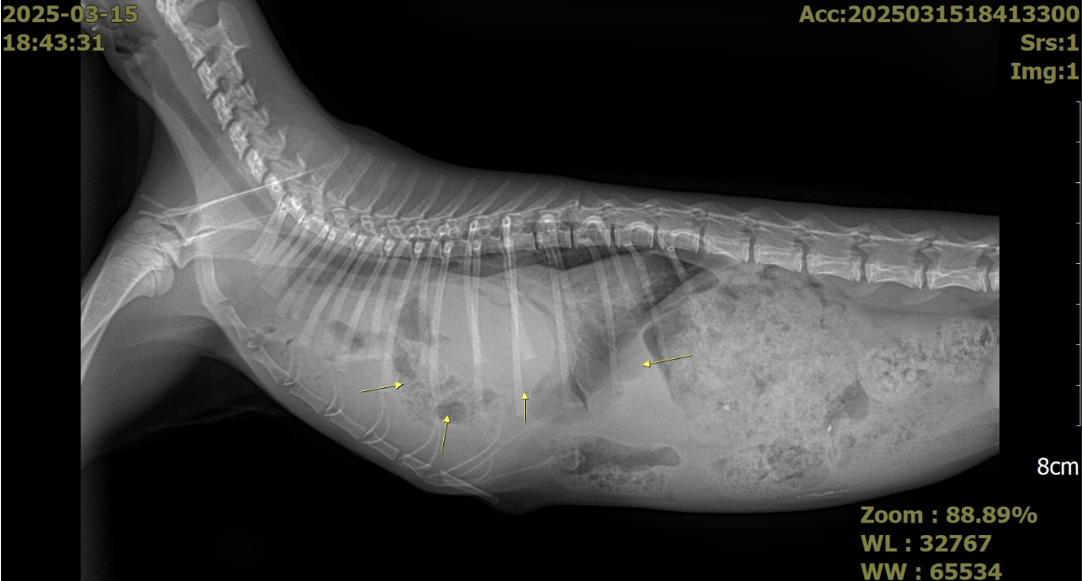

흉부 및 복부 X-ray를 촬영한 결과 흉수 및 복수가 모두 확인되었으며 심장 주변에 복강 장기들이 들어차면서 폐가 허탈되어 있는 모습을 확인할 수 있었습니다.

특히 폐 음영이 정상적으로 나타나는 부위가 없어, 호흡 곤란의 원인을 쉽게 확인할 수 있었습니다.

초음파 검사에서도 심장 옆 흉강 공간에서 간과 장이 발견되었으며 특히 간의 울혈이 확인되었습니다.